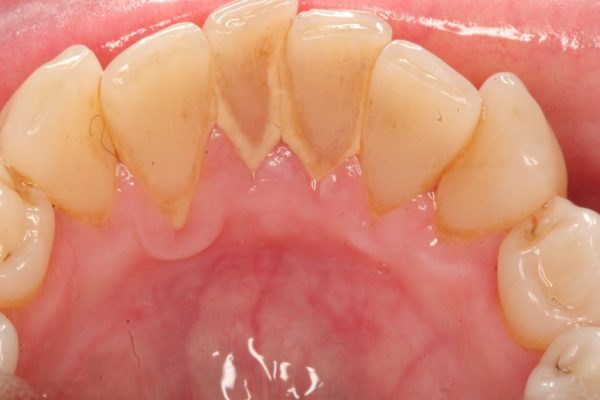

🔴 Cao răng màu vàng nhạt: Đây là màu sắc cao răng cơ bản nhất và phổ biến ở nhiều người. Loại cao răng này được hình thành từ cặn thức ăn và muối vô cơ cùng vi khuẩn, bám vào thân răng (thường ở mặt sau) và nếu để lâu sẽ lan xuống phần nướu chân răng bên dưới.

➤ Cao răng màu vàng nhạt gây mất thẩm mỹ khi cười nói, giao tiếp. Đồng thời, những mảng bám cao răng còn là tác nhân gây mùi hôi miệng khó chịu và là khởi nguồn cho tình trạng viêm nướu (lợi), chảy máu và khiến chính bản thân chúng bị chuyển màu.